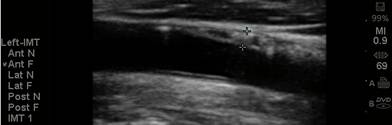

The CIMT procedure is

simple. An ultrasound study is carried out of the carotid arteries in your

neck. A specialized software program is used to precisely measure the mean and

maximum IMT. Standard carotid ultrasound is looking for “flow-limiting”

stenoses, narrowings that could be addressed surgically. This is not what we

are interested in with CIMT testing - we will be measuring soft plaque

accumulation in non-overtly diseased vessel segments (if plaque is identified we

measure the CIMT at an adjacent, normal appearing segment). While the presence

of plaque obviously has significance, it is the IMT parameter that best predicts

the presence and severity of atherosclerotic vascular disease elsewhere in your

body, it’s risk of progression, and your risk of sustaining an atherosclerotic

event (think of IMT as the “staging ground” for obstructive plaque – the higher

the IMT, the greater the rate of IMT progression, the more rapidly will large,

obstructive plaques form). Over 2,000 studies (go to www.pubmed.gov and enter

Carotid IMT) document the link between CIMT and current risk, and an even more

powerful relationship between the rate of change in CIMT and future risk. We

will use CIMT to help us decide who should be treated with preventive measures

and how aggressive our efforts should be. We will use the rate of change of

CIMT to gauge the success of the regimens that we construct for you.